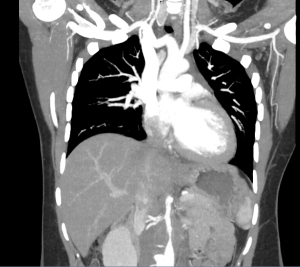

Patient underwent CT angiogram of her chest and abdomen emergently and the findings were suspicious for “periaortitis in association with midaortic syndrome with severe stenosis/near occlusion of the infrarenal aorta, bilateral renal arteries, celiac trunk, and SMA.” Findings that could represent a vasculitis versus neoplastic process.

Aorta narrowing on CT

Narrowing of aorta recon